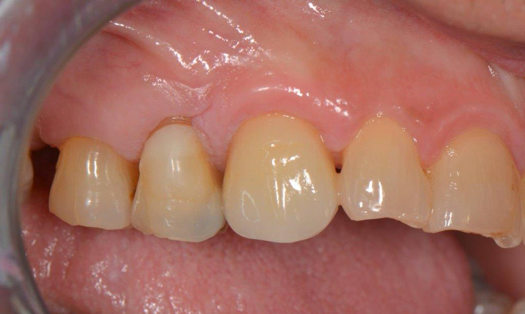

Fig 18. Preoperative image.

Figure 18

Occasionally dentists are presented with extreme challenges with long-term restorations and replacing missing teeth. Dentists must evaluate the patient's condition, develop optimum long-term oral health, and attempt to meet the patient's expectations. Figure 18 showed a class III malocclusion with deep bite, multiple abfractions, and less-than-ideal occlusal plane, but the patient wanted to replace his maxillary right canine only. A discussion with the patient regarding occlusal disharmonies and comprehensive recommendations for full-mouth rehabilitation revealed that the patient had a limited budget for dental care. The patient understood the ramifications of his comprehensive dental needs not being affordable. Decisions were made to atraumatically remove the maxillary right canine (Figure 19) and immediately place a ceramic dental implant (Figure 20). Polytetrafluoroethylene (PTFE) 4-0 sutures were placed to help support soft tissues, and then a full-arch Essix-style retainer with a flowable composite facial veneer was used to provide some esthetics during the patient's healing phase (Figure 21). The implant and the retainer were not to be in contactthe retainer may occlude with the opposing dentition and also be passive in relation to the ceramic implant.